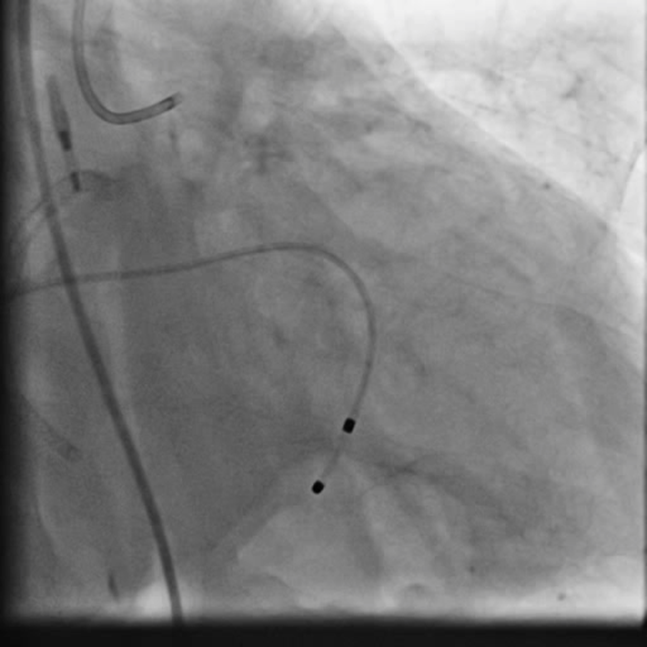

PCIof right coronary artery was initiated on IABP support with amplatz left1 guided catheter and vessel was crossed with great difficulty in repeatedattempts by fielder XT followed by GAIA 2 wire over corsair microcatheter. Microcathetercould not be crossed beyond mid segment calcified CTO, so balloon dilation with0.75 mm balloon was done after which again microcatheter could not be trackedbeyond mid part. Butwe were able to exchange wire to allstar followed by rotawire byplacing microcatheter in mid segment after balloon dilation by 0.75 mm balloon. Rotablation wasdone with 1.25 mm burr at 1,60,00 rpm repeatedly from proximal to mid distalpart. Lesionstill looked unprepared as repeated postdilation with2.25*15 mm followed by 2.5*15 mm non compliant balloon at high pressures showedunexpanded balloon. Againlesion preparation was done with 2.5*15 mm wolverine cutting balloon repeatedlyat high pressures which led to adequate luminal gain and calcium cracks as seenon IVUS run. AfterIVUS run again high pressure balloon dilation was done with wolverine 2.5*15 mmballoon followed by 2.5*12 mm non compliant balloon at 28 atm toadequately prepare the lesion before stent deployment. Stentingwas done with 2.5*32 mm DES, 2.75*32 mm DES, and 3*24 mm DES from distal toproximal in overlapping fashion. Thenfinally high pressure post dilation was done with 2.75*15 mm followed by 3*15mm non compliant balloon and adequate stent expansion was achieved with TIMI 3 flow.